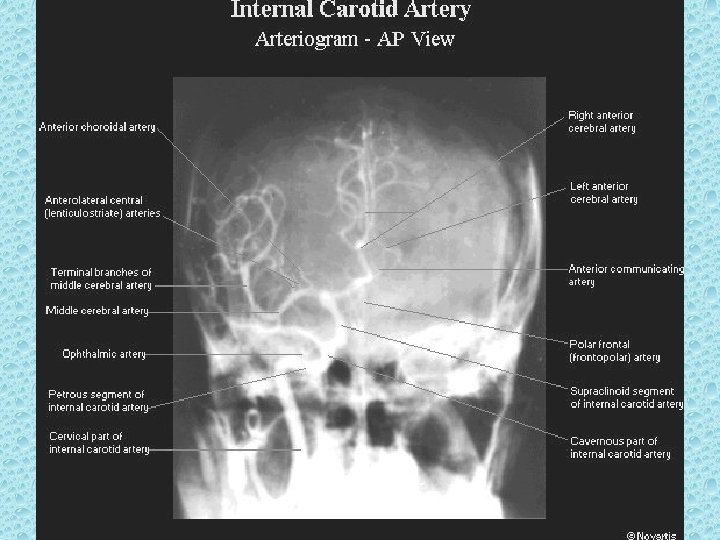

KAFA İÇİNİ BESLEYEN ARTERLER • Bilateral karotid sistem: İnternal karotid arter - A. oftalmika, a. kommunikans posterior, a. koroidea, a. serebri anterior ve media • Vertebrobaziler sistem: Vertebral arterler ve baziller arterlerden oluşur - A. Serebellaris posterior inferior (pica), anterior inferior (aica), a. serebellaris superior, a. serebri posterior

WILLIS POLİGONU • • • Bilateral internal karotid arter Bilateral anterior serebral arter Anterior kommunikan arter Bilateral post. Kommunikan arter Bilateral post serebral arter